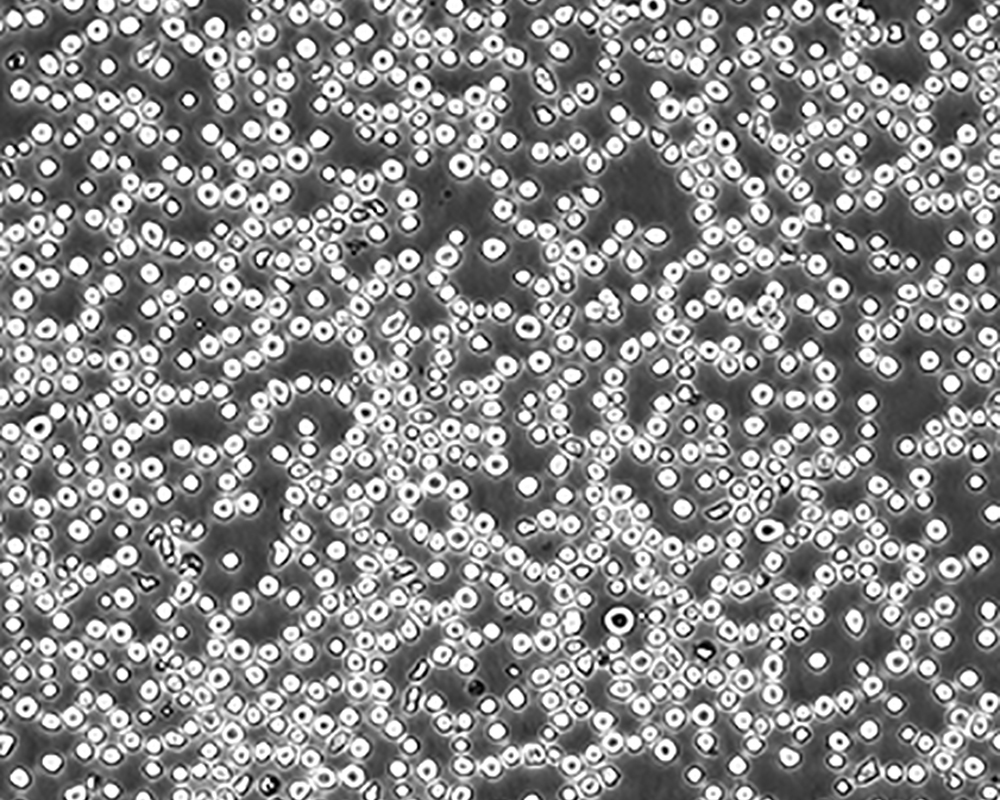

生長特性 suspension

形態特征 lymphoblast

傳代方法 1:2-1:4

細胞描述 CEM/C1是人T細胞白血病細胞株CCRF-CEM(見ATCC CCL-119)具有喜樹堿抗性的衍生株。1991年細胞株選擇并亞克隆了對CPT的抗性。細胞表現出對CPT類似物水溶性的托泊替康和非水溶性的9-氨基-CPT及10,11-亞甲二氧基-CPT具有交叉抗性。CEM/C1細胞對CPT的敏感性較母系CEM細胞低31倍。CEM/C1細胞表現非典型的多藥抗性和轉換拓補異構酶I催化活性。對CPT的抗性維持6個月以上。

細胞傳代步驟 如果細胞密度達80%-90%,即可進行傳代培養。1. 棄去培養上清,用不含鈣、鎂離子的PBS潤洗細胞1-2次。2. 加2ml消化液(0.25%Trypsin-0.53mM EDTA)于培養瓶中,置于37℃培養箱中消化1-2分鐘,然后在顯微鏡下觀察細胞消化情況,若細胞大部分變圓并脫落,迅速拿回操作臺,輕敲幾下培養瓶后加少量培養基終止消化。3. 按6-8ml/瓶補加培養基,輕輕打勻后吸出,在1000RPM條件下離心4分鐘,棄去上清液,補加1-2mL培養液后吹勻。4. 將細胞懸液按1:2到1:5的比例分到新的含8ml培養基的新皿中或者瓶中